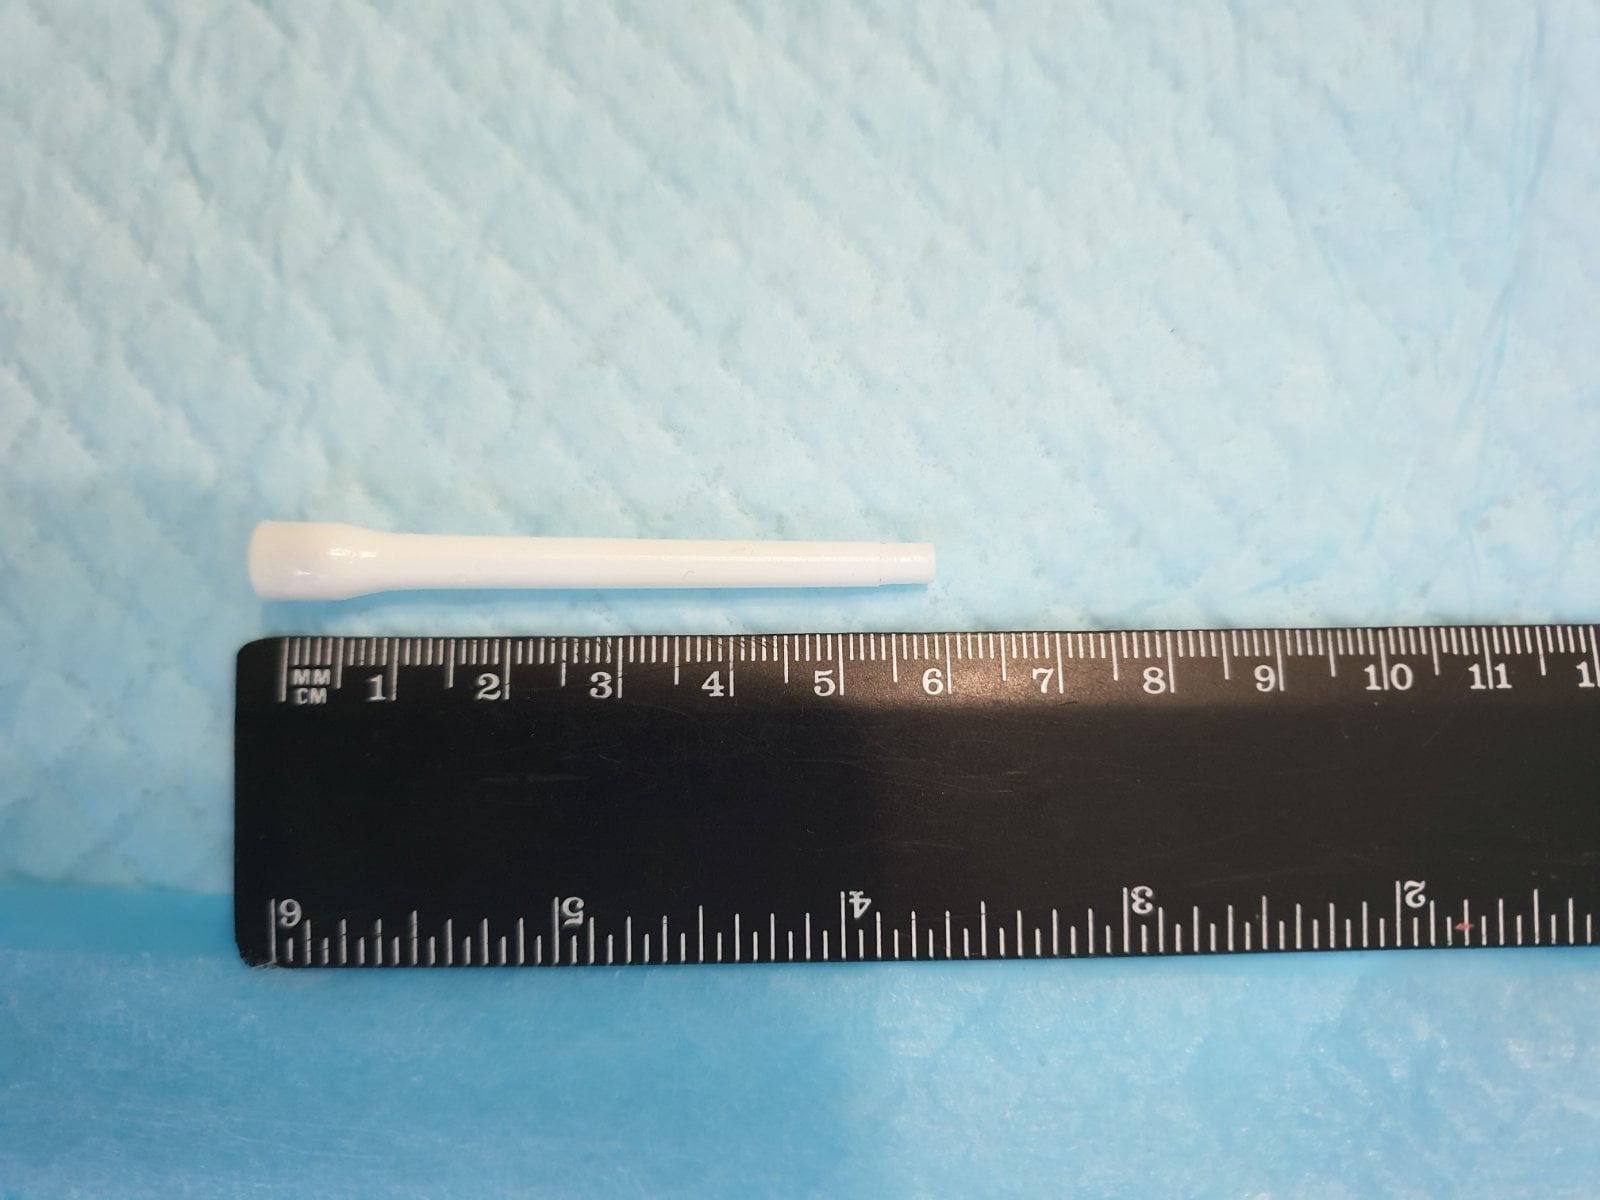

Предмет длиной 6 см оказался аж в двенадцатиперстной кишке. Госпитализированного парня сразу взяли в операционную, где врачи эндоскопически, с помощью специальных устройств, без всякого разреза вытащили распылитель.